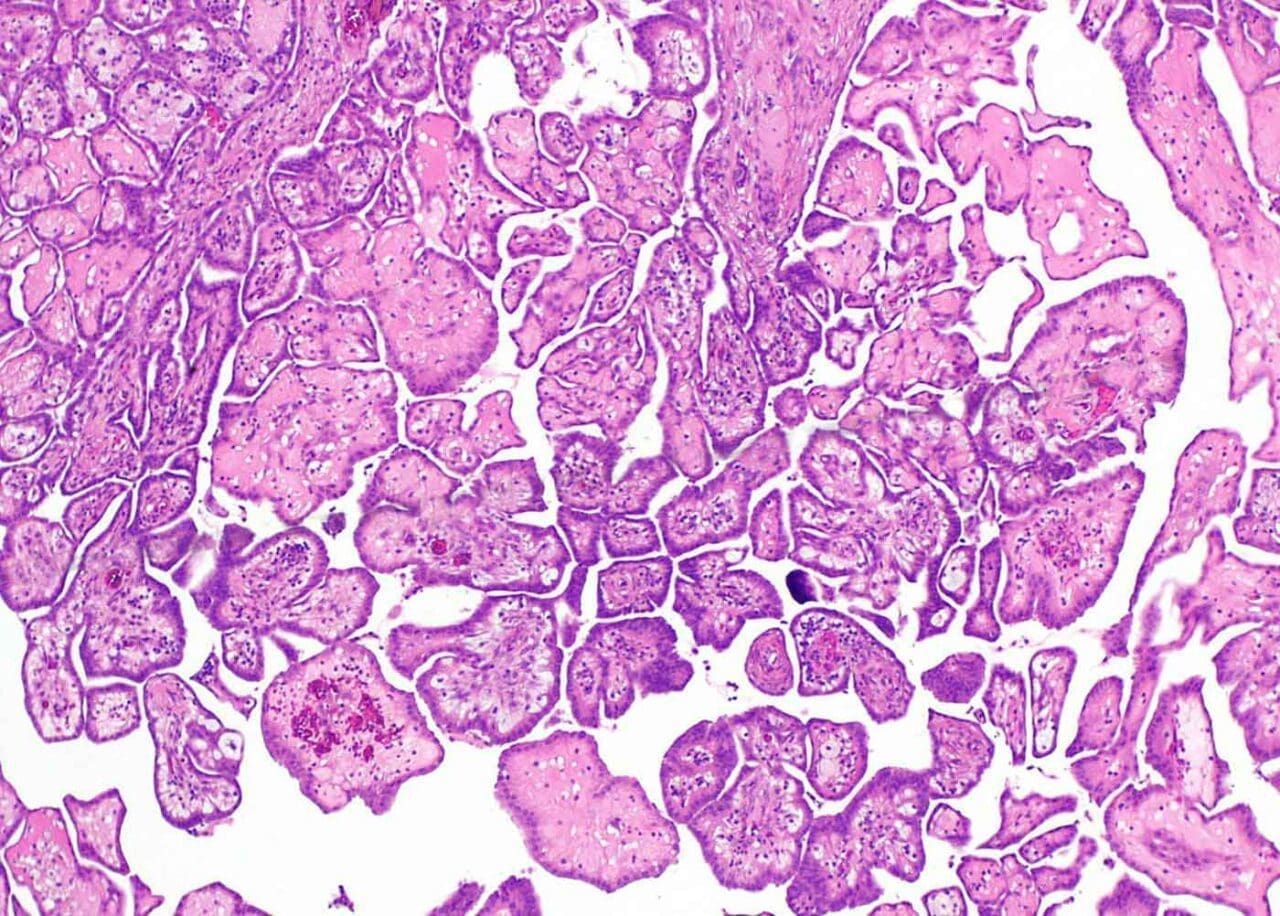

The Different Faces: Mesothelioma Cell Types Under Microscope

Mesothelioma isn't a single entity; it comes in different cellular forms, each with its own microscopic appearance. Pathologists meticulously examine these cells to classify the mesothelioma. Understanding these types is key for tailoring effective treatment strategies.

The main types of mesothelioma cells seen under the microscope include:

- Epithelioid Mesothelioma: This is the most common type, accounting for about 50-70% of cases. These cells often look somewhat uniform and form gland-like structures or sheets, resembling normal epithelial cells. They typically have a better prognosis compared to other types.

- Sarcomatoid Mesothelioma: Less common, making up 10-20% of cases. These cells are spindle-shaped, resembling connective tissue cells, and can be more aggressive. They often appear disorganized and spread more readily.

- Biphasic Mesothelioma: As the name suggests, this type contains a mixture of both epithelioid and sarcomatoid cells. Its prognosis depends on the proportion of each cell type present in the tumor sample.